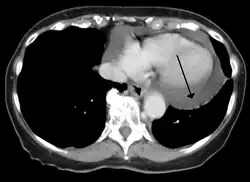

Cardiac CT and MRI scans: cross-sectional imaging with computed tomography (CT) can help localize and quantify the effusion, especially in a loculated effusion (an effusion contained to one area).[12] CT imaging also helps assess for pericardial pathology (pericardial thickening, constrictive pericarditis, malignancy-associated pericarditis).[1] Whereas cardiac MRI is reserved for patients with poor echocardiogram findings and for assessing pericardial inflammation, especially for patients with continued inflammation despite treatment.[5] CT and MRI imaging can also be used for continued follow up on patients.

A CT scan showing a pericardial effusion